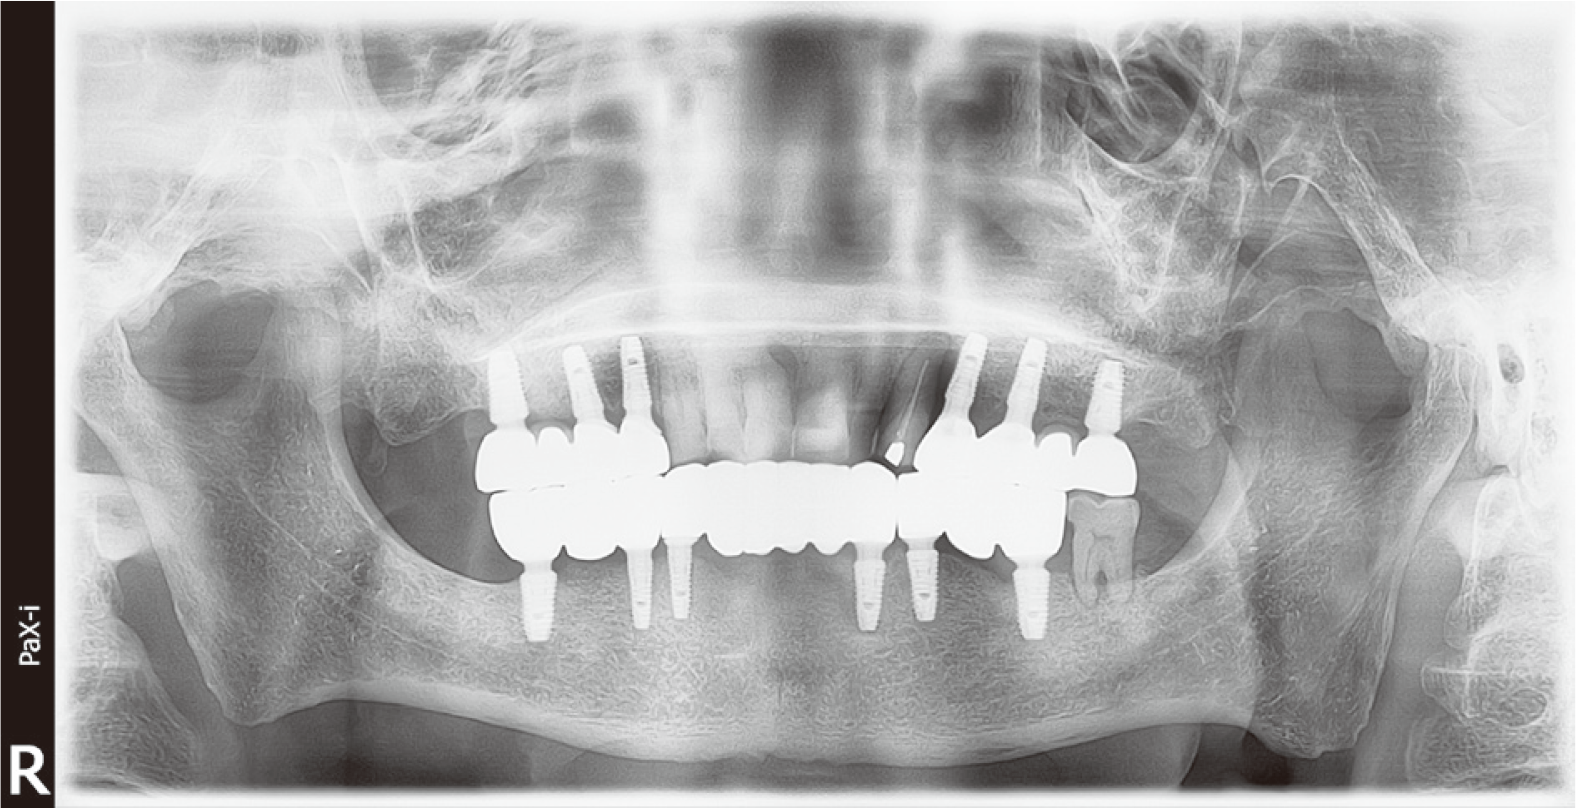

60세 남자 환자로 전체적인 치과치료를 위해 본원에 내원하였다. 환자는 의과적으로 기질성 정신장애를 진단을 받았으며, 거동이 불편하고 보행이 불가능하여 요양병원에서 입원 치료 중이었다. 정신건강의학과에서 환자의 정신장애에 대해 치료상태가 안정된 상태임을 확인한 후, 치과치료를 진행하였다. 파노라마 방사선 사진 및 구강검사에서 상악 우측 제1소구치와 제1대구치, 좌측 제제1, 2소구치, 하악 우측 제1대구치에 잔존 치근이 존재하였으며, 상악 우측 견치와 하악 좌측 견치 및 소구치에서 치아우식증이 관찰되었다(Fig. 1). 환자의 의과적 병력과 치료의 협조도, 구강위생 조절 능력 등을 고려했을 때, 가철성 보철물의 유지와 관리가 어렵다고 판단되어 고정성 보철물로 수복을 계획하였다. 예후가 불량한 상악 우측 견치, 제1소구치, 제1대구치와 좌측 제제1, 2소구치, 하악 좌측 견치, 제1소구치와 우측 1대구치를 발치 한 후, 치아 상실부위에 임플란트 식립을 하였고(Fig. 2), 골유착 기간을 거쳐 최종인상을 채득하였다. 제작한 임플란트 보철물을 장착하던 과정에서 치과의사는 하악 우측 제제1, 2소구치와 제1대구치로 이루어진 3본 지르코니아 보철물이 환자의 구강 내로 떨어뜨렸고, 떨어진 즉시 환자의 두부를 좌측으로 돌려 환자가 보철물을 삼키지 않도록 노력하였으나, 환자가 보철물을 삼키게 되었다. 환자가 보철물을 삼킨 이후 기침이나 구토 반사 등의 특이적 소견을 보이지 않았으며, 호흡상태는 양호하였다. 환자 보호자에게 보철물 장착과정에서 보철물을 구강 내로 떨어뜨렸고, 이후 삼킴이 발생하였음을 설명하였다. 그리고 삼켜진 보철물의 위치 확인을 위하여 인근 내과로 전원 의뢰를 시행하였다. 전원 의뢰된 당일, 내과에서 복부 방사선 사진을 촬영하였고, 판독 결과 보철물이 위장에 위치를 하고 있음을 확인하였다. 24시간 이후 배출될 것으로 예상되어 48시간 후 재촬영이 필요할 것이라는 회신서를 확인하였다(Fig. 3). 2일 후 환자를 내원하도록 하여 추가로 복부 방사선 사진을 촬영하였다. 방사선 사진에서 위장관 내에서 보철물 확인되었다. 환자의 거동이 불편하여 위장관 운동이 저하되어 있는 상태이기 때문에 배출이 지연될 수 있다는 의과적 소견을 회신 받았다(Fig. 4). 8일 후 환자의 복부 방사선 사진을 촬영하였으며, 보철물이 위장관에서 완전히 배출되어 체 내에 있지 않음을 확인하였다(Fig. 5). 이 후 하악 우측 제1, 2소구치와 제1대구치에 새로운 보철물을 제작하여 최종 합착(Rely-X, 3M ESPE, St Paul, USA)을 시행하였다(Fig. 6).